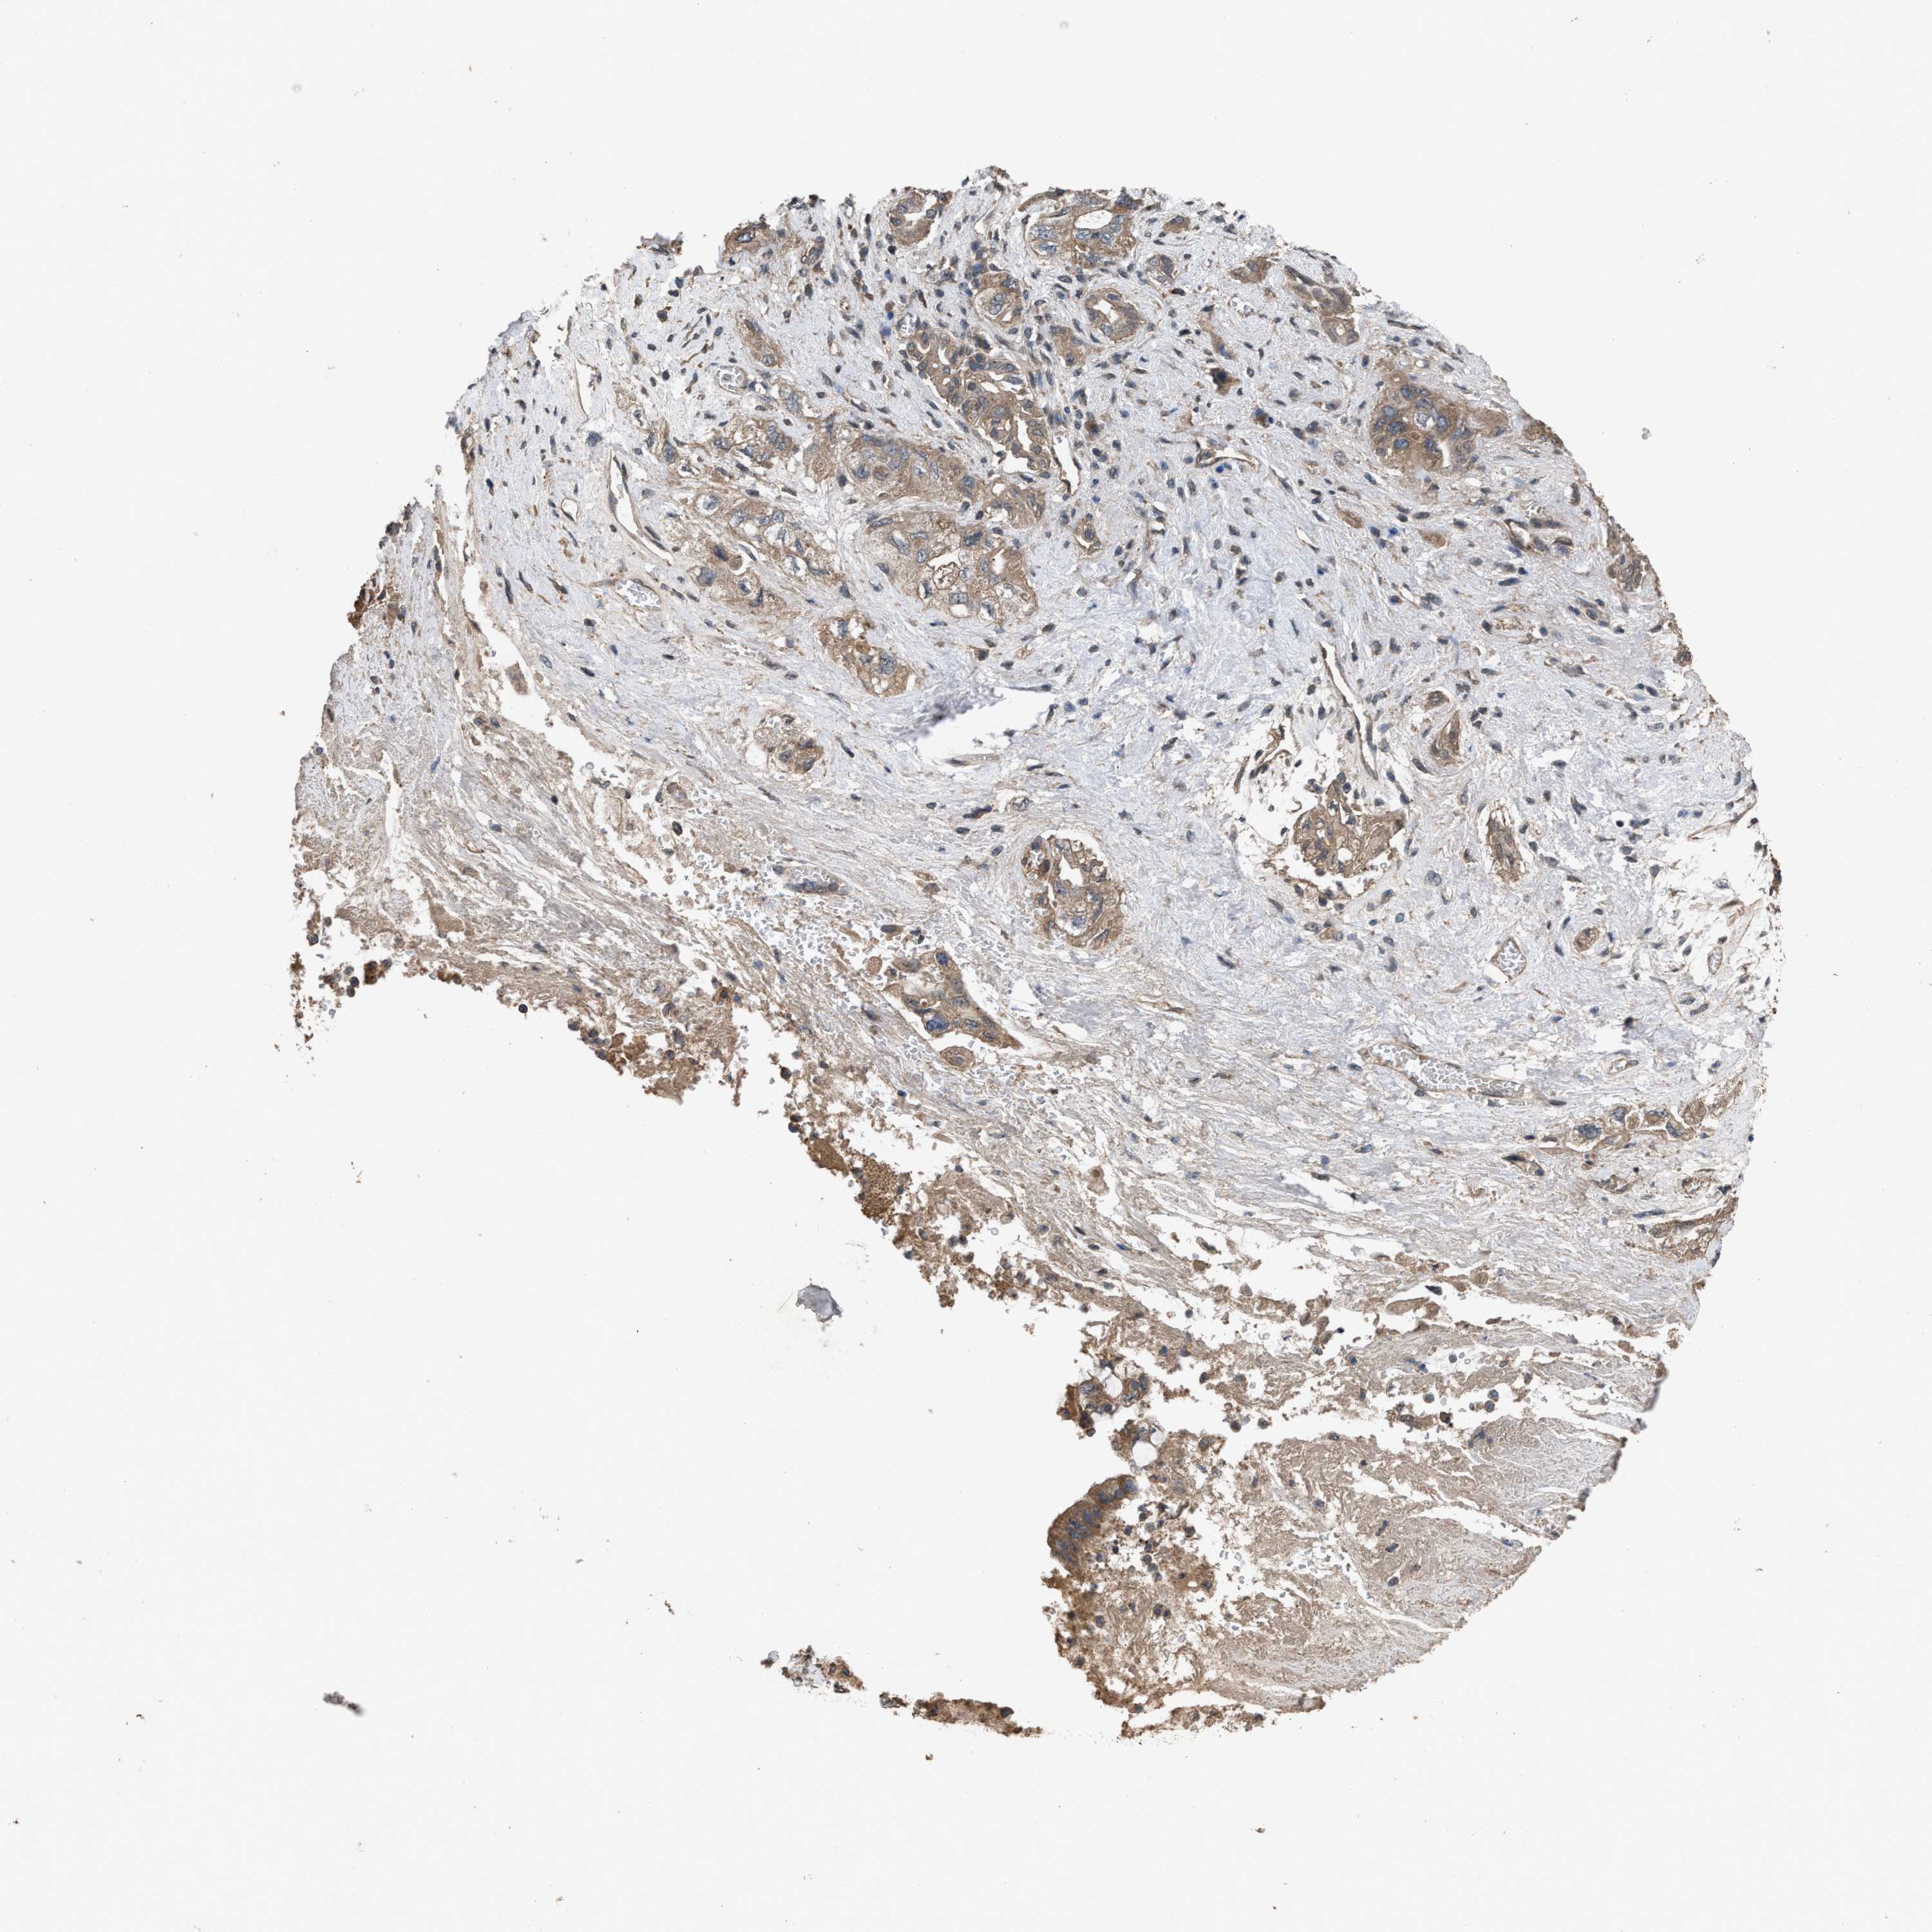

PANCREATIC CANCER - Protein expressioni

A mouse-over function shows sample information and annotation data. Click on an image to view it in a full screen mode. Samples can be filtered based on level of antibody staining by selecting one or several of the following categories: high, medium, low and not detected. The assay and annotation is described here.

Note that samples used for immunohistochemistry by the Human Protein Atlas do not correspond to samples in the TCGA dataset.

Antibody stainingi

Antibody staining in the annotated cell types in the current human tissue is reported as not detected, low, medium, or high, based on conventional immunohistochemistry profiling in selected tissues. This score is based on the combination of the staining intensity and fraction of stained cells.

Each image is clickable and will lead to virtual microscopy that enables deeper exploration of all samples and also displays staining intensity scores, fraction scores and subcellular localization as well as patient and tissue information for each sample.

Antibody HPA018894

Antibody CAB016348

Staining

High

Medium

Low

Not detected

Intensity

Strong

Moderate

Weak

Negative

Quantity

>75%

75%-25%

<25%

None

Location

Nuclear

Cytoplasmic/membranous

Cytoplasmic/membranous,nuclear

Adenocarcinoma, NOS